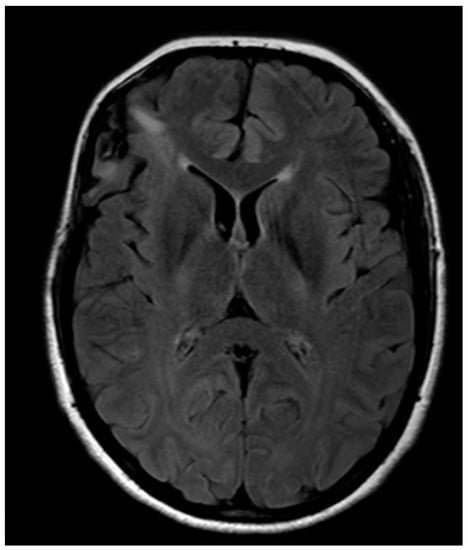

Histology provided evidence for isocitrate dehydrogenase 1(IDH1)-mutated, ATP-Dependent Helicase (ATRX)-wild diffuse low-grade astrocytoma. Postoperative MR showed a subtotal removal with residual disease where IFOF was intraoperatively identified (Figure 5). No adjuvant therapy was then proposed, and the patient is currently fully working. If evidence of residual disease progression is observed, a new surgery will be proposed, delaying eventual adjuvant therapy as much as possible.

Figure 5. Post-operative anatomical MRI.